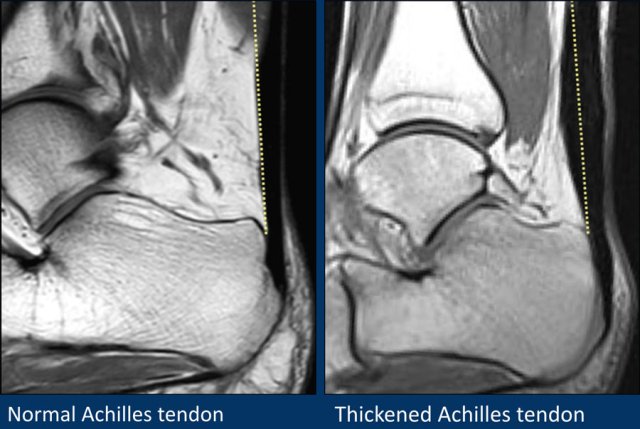

Achilles tendon

Achilles tendinopathy is most likely due to a series of microtears that weaken the tendon and cause swelling of the tendon (image on the right).

On sagital images the achilles tendon should be a straight line without any fluid around it and no focal thickening.

A transverse diameter of 8 mm is the cut off.